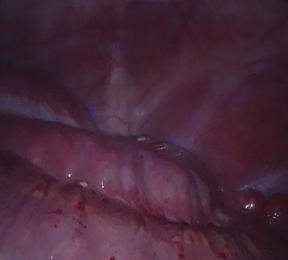

Validation in real endoscopies. We used the Hamlyn dataset [30], that contains intracorporeal endoscopic RGB scenes with weak textures, deformations and reflections. Specifically, we chose scenes 1 and 17 (see Figure LABEL:fig:hamlyn), which are significant exploratory ones. Most of Hamlyn’s videos have very small camera motions, being of no interest for benchmarking odometry methods. We slightly cropped the images to remove black pixels at the borders. Depth data was taken from the public tracking test data of EDaM [9] which was estimated by a single-view dense depth network trained in a self-supervised manner in all Hamlyn scenes except for the test ones. Note that this depth does not have the same quality as the real ground truth one from the Drunkard’s Dataset.

Refer to caption

(a) Scene 1 frame

(b) Scene 17 frame

(e) APTEksubscriptAPTE𝑘\mathrm{APTE}_{k} plots in Hamlyn’s scene 1.

[Uncaptioned image]

(f) APTEksubscriptAPTE𝑘\mathrm{APTE}_{k} plots in Hamlyn’s scene 17.

Figure 4: Camera tracking performance on the Hamlyn dataset. APTEksubscriptAPTE𝑘\mathrm{APTE}_{k} values along the N𝑁N different k𝑘k-frames-length-loops in Hamlyn’s scenes 1 (a) and 17 (b) for EDaM [9], DROID-SLAM [34] and Drunkard’s Odometry (ours) with and without having been trained in deformable scenes of the Drunkard’s Dataset (i.e. trained in level 1 and 0, respectively). The training on deforming scene substantially improves the performance of our method.